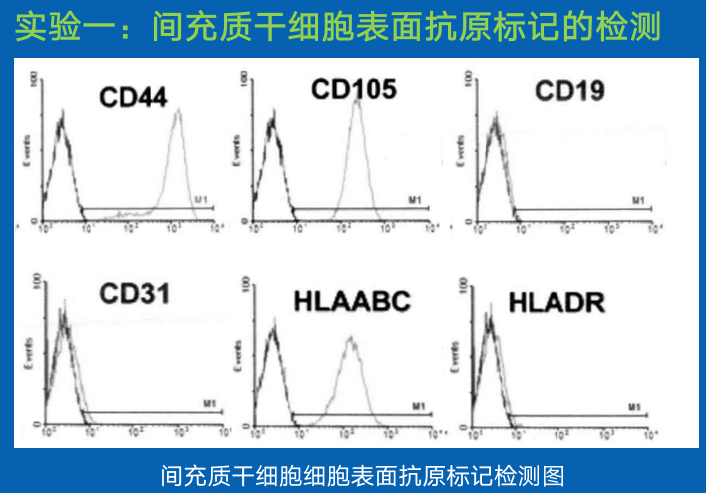

选择传代培养生长状态良好,处于对数增长期的脐带间充质干细胞,经0.2%胰酶消化制成单细胞悬液进行流式细胞术检测其表面抗原的表达情况。

结论:

流式细胞仪检测所制备的间充质干细胞的表面表达抗原 CD44、CD105 以及 I 类抗原 HLA-ABC,但是不表达 CD19、CD31 以及 II 类抗原HLA-DR,证明制备的间充质干细胞正常。